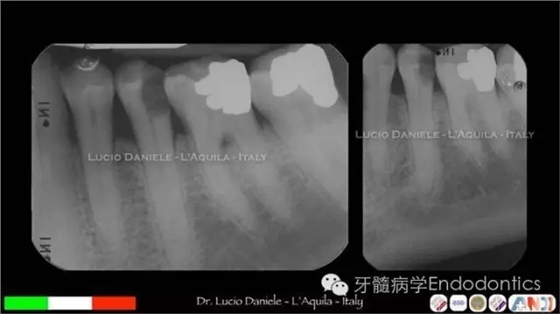

圖1. MTA直接蓋髓

圖2.